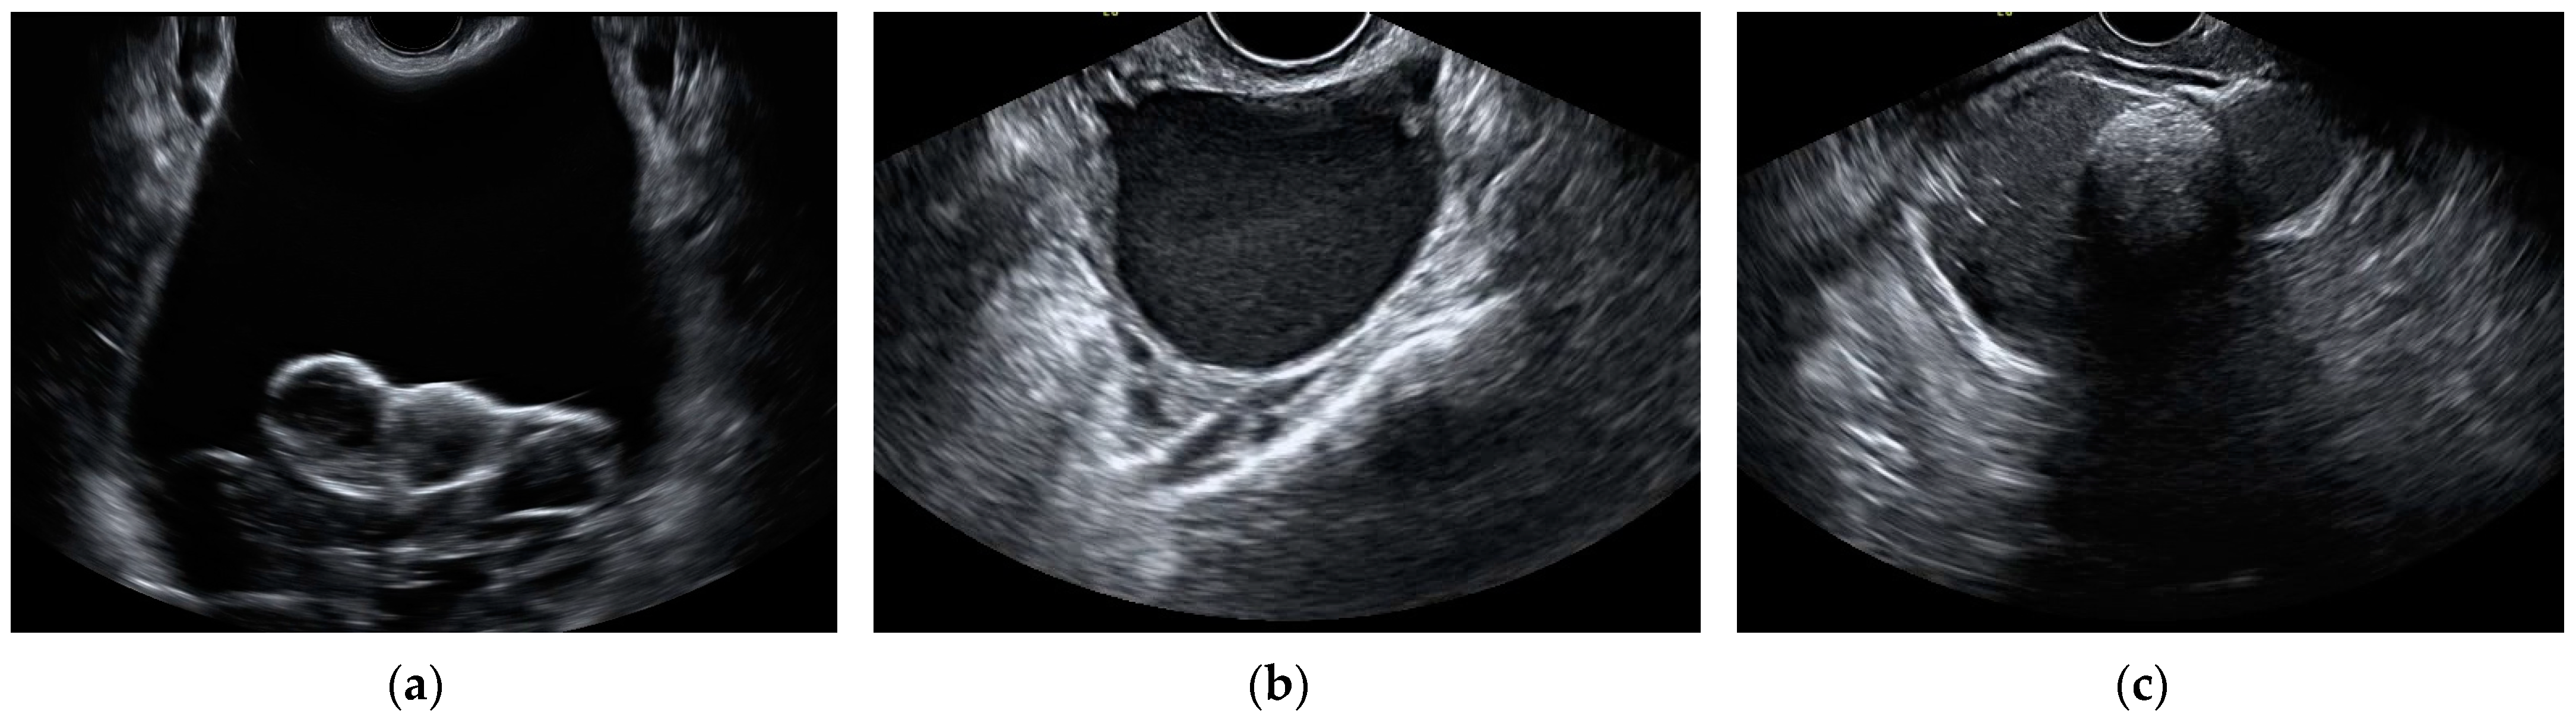

Figure 6.

Still ultrasound images of benign ovarian masses misclassified as malignant by the aggregate model. (a) Serous cystadenoma, (b) endometrioma, and (c) mature cystic teratoma.